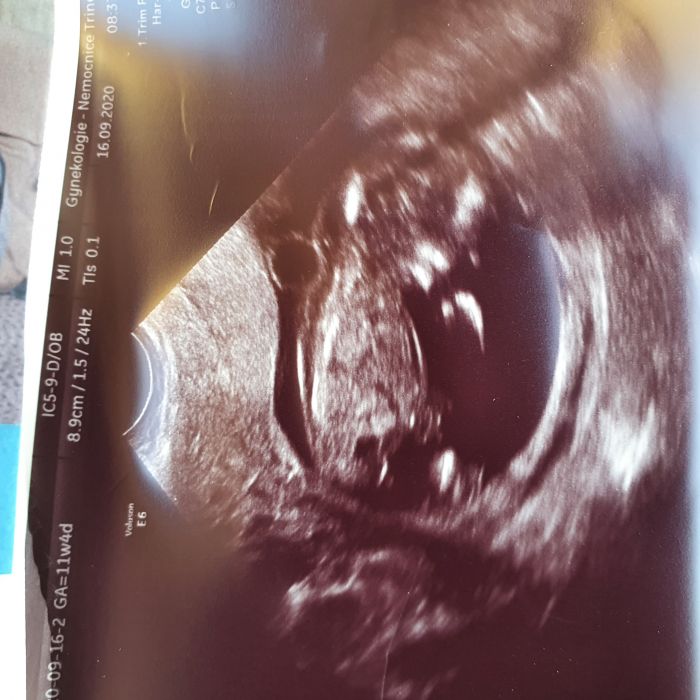

Ahojte holky, přidávám se k vám, dnes sem 11+0 a screening mám 23.9. je to moje druhé těhotenství. Doma už máme 26 měsíčního chlapečka :)... Dnes sem se po dlouhé době vážila a už sem 3 kila shodila díky nevolnostem. Ale musím fungovat. Dodelavame domeček, tak už to uhanim a maka m s chlapama, aby se druhé mimco narodilo do nového. Chtěla bych se stěhovat na vánoce, tak snad to klapne.